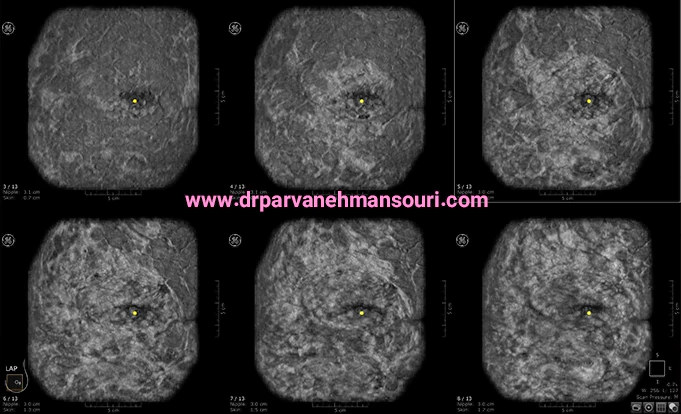

سونوگرافی پستان، یکی از روش های تشخیص سرطان پستان است که با تاباندن امواج صوتی به بافت سینه، تصاویری را از قسمت داخلی سینه تولید می کند. نوع دیگری از سونوگرافی تحت عنوان سونوگرافی داپلر وجود دارد که دید دقیق تری در خصوص وضعیت پستان ها می دهد. در این نوع سونوگرافی، نحوه حرکت خون در رگ ها بررسی می شود و در صورت در جریان بودن خون در توده ها، می تواند به پزشک آگاهی های لازم را بدهد.

پس از معاینه فیزیکی، ژل سونوگرافی بر روی ناحیه مورد نظر مالیده می شود. کارکرد این ژل افزایش توانایی حرکتی امواج صوتی است. به این صورت که حبابهای هوا را محدود می کند و از طریق بافت ها باعث افزایش این توانایی میشود. پزشک ممکن است چراغ های اتاق را خاموش کند تا صفحه رایانه مشخص تر به نظر برسد. پس از مالیدن ژل بر روی ناحیه مورد نظر، از یک مبدل کوچک برای ارسال امواج به پستان و ثبت نتیجه استفاده می شود. هنگامی که یک موج صوتی به یک بافت یا ساختار برخورد می کند، برگشت می کند.

مبدل اطلاعاتی را در مورد اینکه چقدر طول کشیده است تا این امواج برگردند و سایر مشخصات مربوطه را بر روی رایانه نمایش می دهد. رایانه این اطلاعات را به صورت تصاویری نمایش می دهد. متخصص سونوگرافی، کل ساختار مورد نظر را از زوایای گوناگون بررسی می کند.

بعد از انجام سونوگرافی، چندین تصویر ثابت از توده تهیه می شود. همچنین ناحیه زیر بغل و غدد لنفاوی نیز بررسی میشوند. در پایان، زمانی به فرد داده می شود که ژل ها را پاک کرده و لباس خود را تنظیم کند. کل فرآیند سونوگرافی 15 الی 30 دقیقه زمان می برد. در نهایت، تفسیر سونوگرافی پستان ها توسط متخصص انجام می شود.